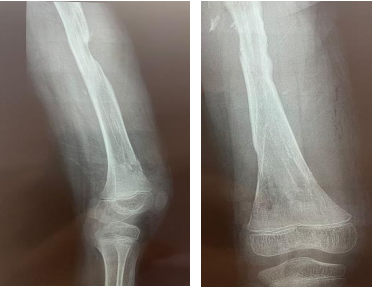

A 10-year-old male patient fell from a height and sustained a direct damage to the shaft of his femur, for which he underwent elastic nail fixation a year ago. He now complains of thigh pain, trouble walking, and knee stiffness for the past six months. On examination, the patient was critically stable, with no head, chest, or abdominal damage, and a normal hip and spine assessment. On local examination, there was swelling with a discharging sinus in the mid-thigh over the anterolateral aspect of 11x4.1 centimetres (superior to inferior and anterior to posterior), with two linear scar marks healed with primary intention over the distal thigh in the medial and lateral aspects, a temperature raised locally, and tendered swelling. Hip joint movements were within normal limits, and knee extension was normal.

All routine investigations were ordered, including an X-ray of the thigh with knee AP and lateral views and an ultrasound for local swelling. On ultrasound, there was a swelling of 11x4.1 centimetres (superior to inferior and anterior to posterior) in the anterolateral part of the mid-thigh, connecting with a sinus measuring 4mm in diameter and not engaging any joint structure.

After suitable painting and draping, an incision was made near the old scar mark on the medial side of the distal thigh under C-ARM control, after tissue dissection, the bone cortex of the medial side of the femur was pierced with a drill, and the end of the elastic nail was felt and retrieved with the use of a T handle. In the case of the lateral side of the elastic nail, an incision was made over the old scar mark, as deepening the incision revealed a collection of pus containing around 200-300 ml. The entire collection was drained and the elastic nail end was felt and retrieved using pliers and a hammer. Irrigation with normal saline and betadine was performed on both sides, and gentamycin was then administered locally. The wound was closed with silk and an antibiotic dressing was applied. Even after the elastic nails were removed, the knee remained stiff.

Figure 3

Figure 4